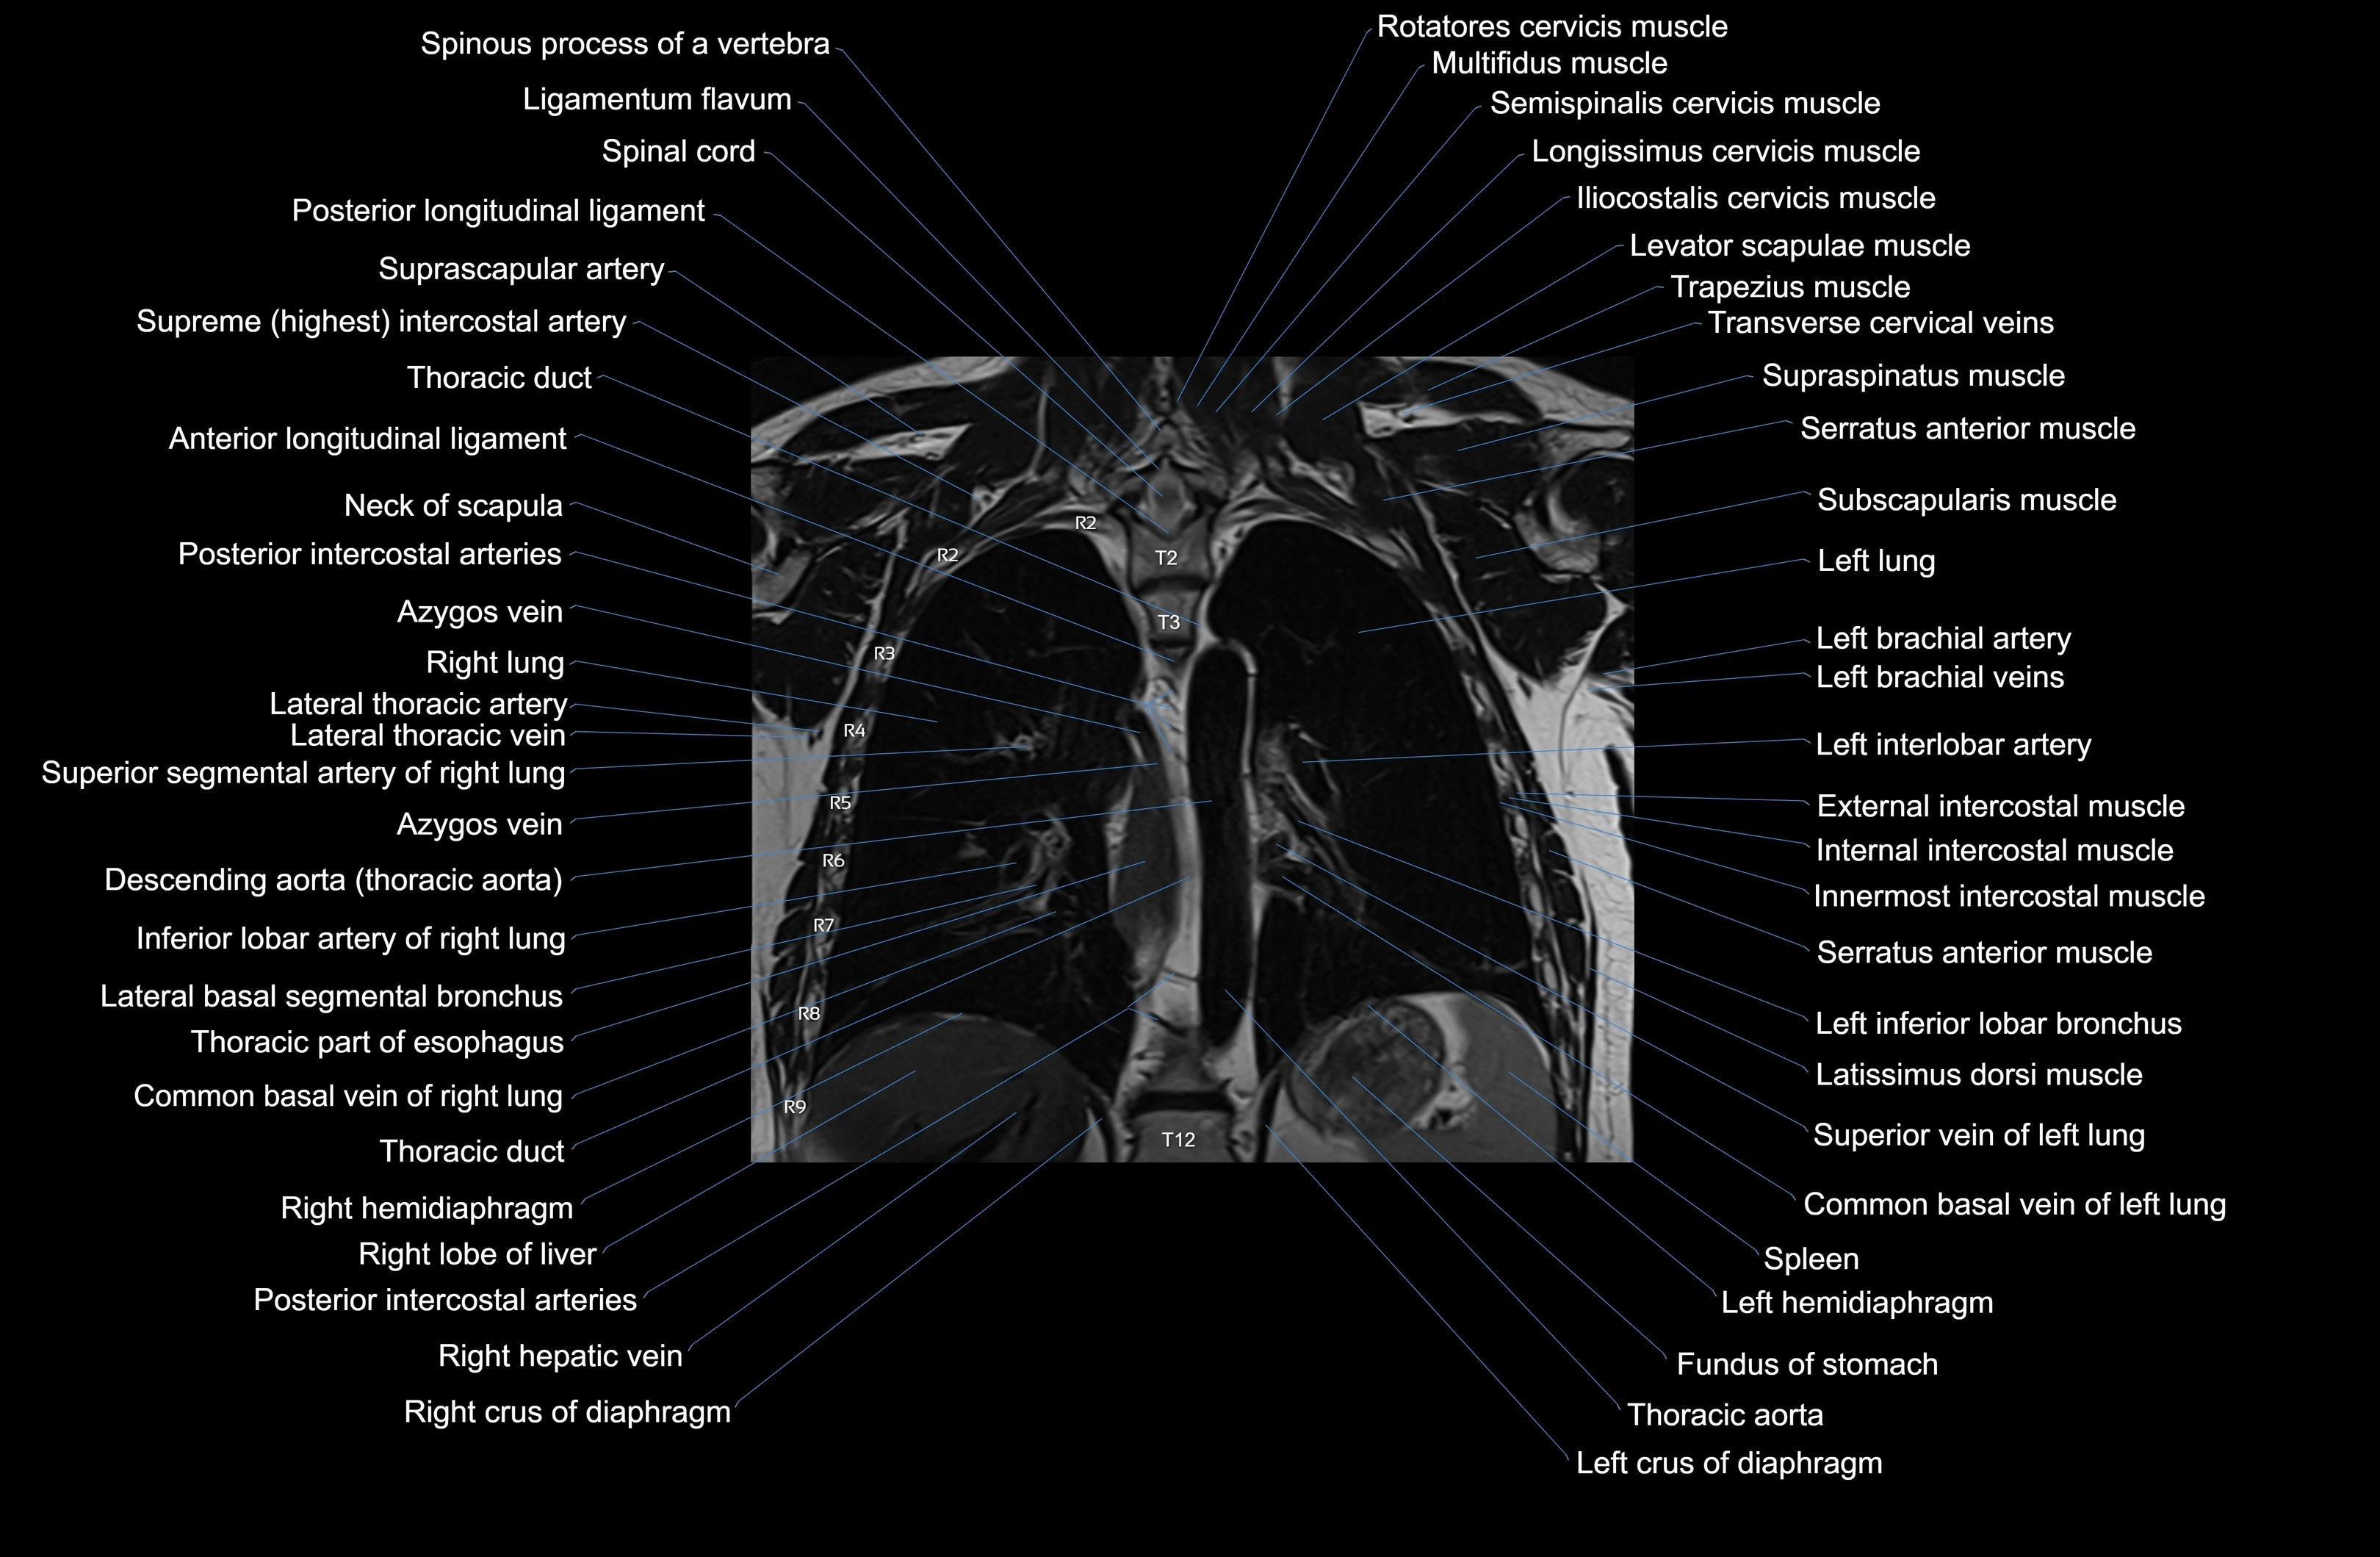

- T (Thoracic spine)